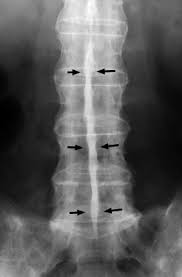

The _____ sign is seen in spinal metastases.